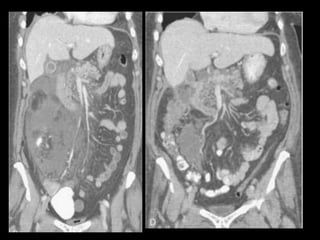

PANCREATITE AGUDA GRAVE

Ocorre em 20-30% dos pacientes com PA;

Caracteriza-se por evolução protraída, insuficiência

de múltiplos órgãos e necrose pancreática;

Necrose pode ser difusa ou esparsa, superficial ou

profunda, e pode afetar qualquer parte do

pâncreas;

A necrose ocorre logo de início, em 24-48 horas,

ela permanece estável, com raras exceções.

Os resultados TC são melhores indicadores

prognósticos que sistemas de escores numéricos,

devido a sua maior sensibilidade e especificidade.

Complicações da PA

1. Coleções líquidas agudas

2. Abscesso pancreático

3. Necrose

4. Hemorragia

Coleções líquidas agudas

Ocorrem em cerca de 40% dos casos;

Podem ser em torno da glândula ou extra-

pancreático;

Carecem de cápsula e são confinadas ao espaço

anatômico onde se encontram;

Podem dissecar para outros locais: mediastino,

pararrenal posterior, órgãos sólidos ou parede de

alça intestinal.